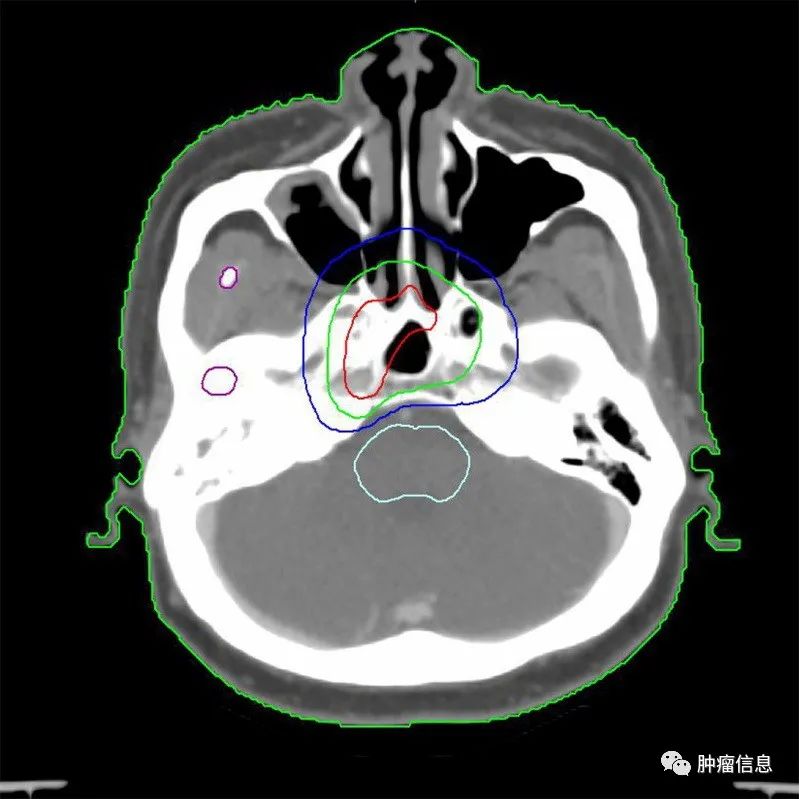

2.靶区勾画示意图

为方便和国际指南对照,靶区采用与国际指南相同的颜色:国际指南的GTVp =本示意图GTVnx;国际指南的GTVn =本示意图GTVnd;国际指南的CTV1 =本示意图CTV1;国际指南的CTV2 =本示意图CTV2。

图2 T3N1M0

注:靶区勾画颜色为GTVnx、GTVnd、CTV1、CTV2。